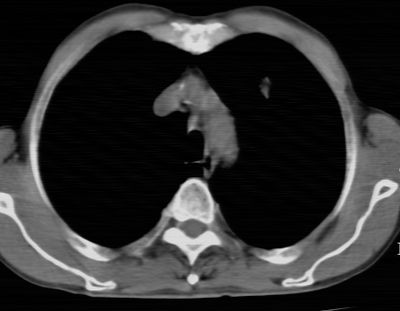

标题: CT24783:m71,既往肺心病史3年,现咳嗽,憋喘。 [打印本页]

标题: CT24783:m71,既往肺心病史3年,现咳嗽,憋喘。

1)左肺上叶周围型肺癌可能。2)两肺全小叶型肺气肿。

左上周围型肺癌,全小叶型肺气肿。